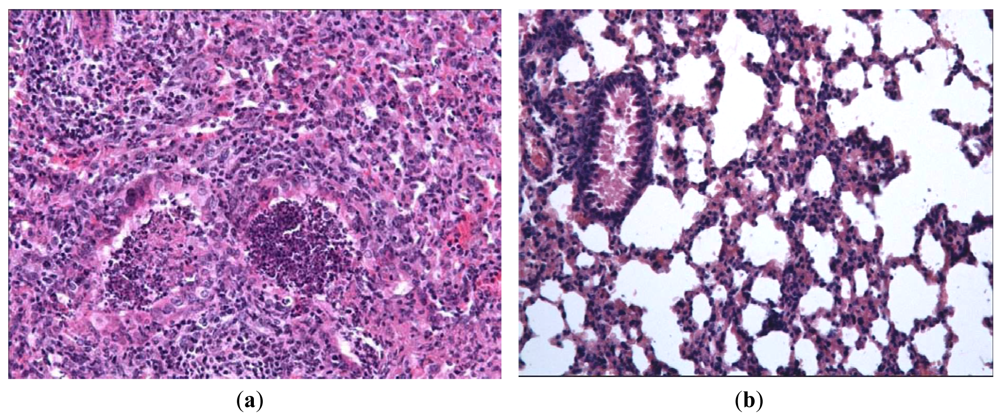

Infecting of Syrian hamsters with human parainfluenza virus (hPIV) results in non- fatal mild bronchitis, bronchiolitis and pneumonia. The virus can be recovered from the lungs on day 3 p.i., and specific tissue damage can be observed on day 7.

Hamsters infected with hPIV showed no observable evidence of illness prior to sacrifice, but histologically there was consistent production of pneumonia. Lung lesions consisted of scattered endobronchial exudates composed of mononuclear and polymorphonuclear cells, peribronchial and perivascular round cell infiltrates, and wide areas of interstitial pneumonia. Bronchial epithelium had a specific appearance containing groups of tall giant cells protruding into the bronchial lumen [Figures 5(a,b)]. Animals treated with Ingavirin and ribavirin demonstrated almost normal lung tissue architecture with few infiltrating cells [Figures 5(c,d)].